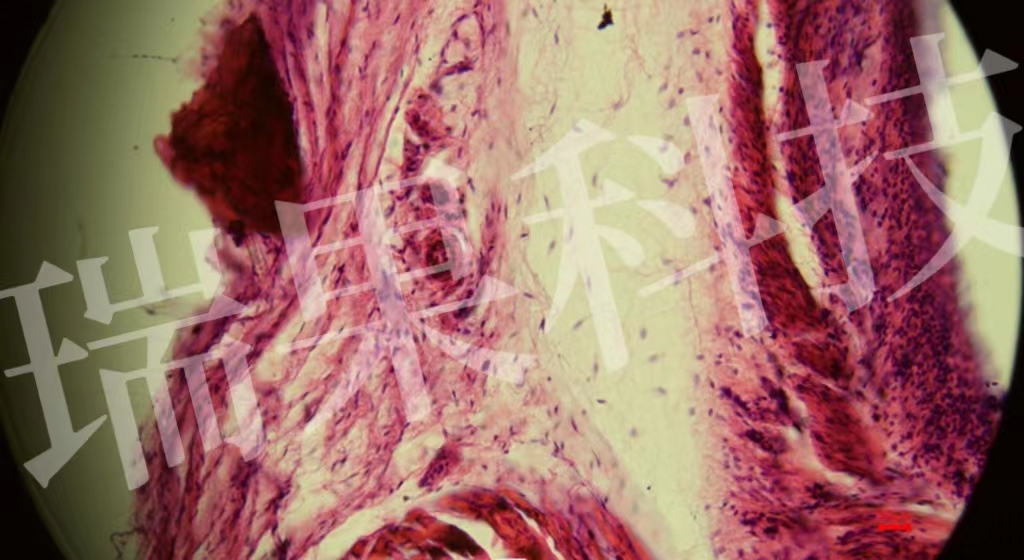

HE染色:苏木精 - 伊红染色法 ( hematoxylin-eosin staining ) ,简称HE染色法 ,石蜡切片技术里常用的染色法之一 。苏木精染液为碱性 ,主要使细胞核内的染色质与胞质内的核酸着紫蓝色 ;伊红为酸性染料 ,主要使细

HE染色:苏木精 - 伊红染色法 ( hematoxylin-eosin staining ) ,简称HE染色法 ,石蜡切片技术里常用的染色法之一 。苏木精染液为碱性 ,主要使细胞核内的染色质与胞质内的核酸着紫蓝色 ;伊红为酸性染料 ,主要使细胞质和细胞外基质中的成分着红色 。HE染色法是组织学、胚胎学、病理学教学与科研中最基本、使用最广泛的技术方法。